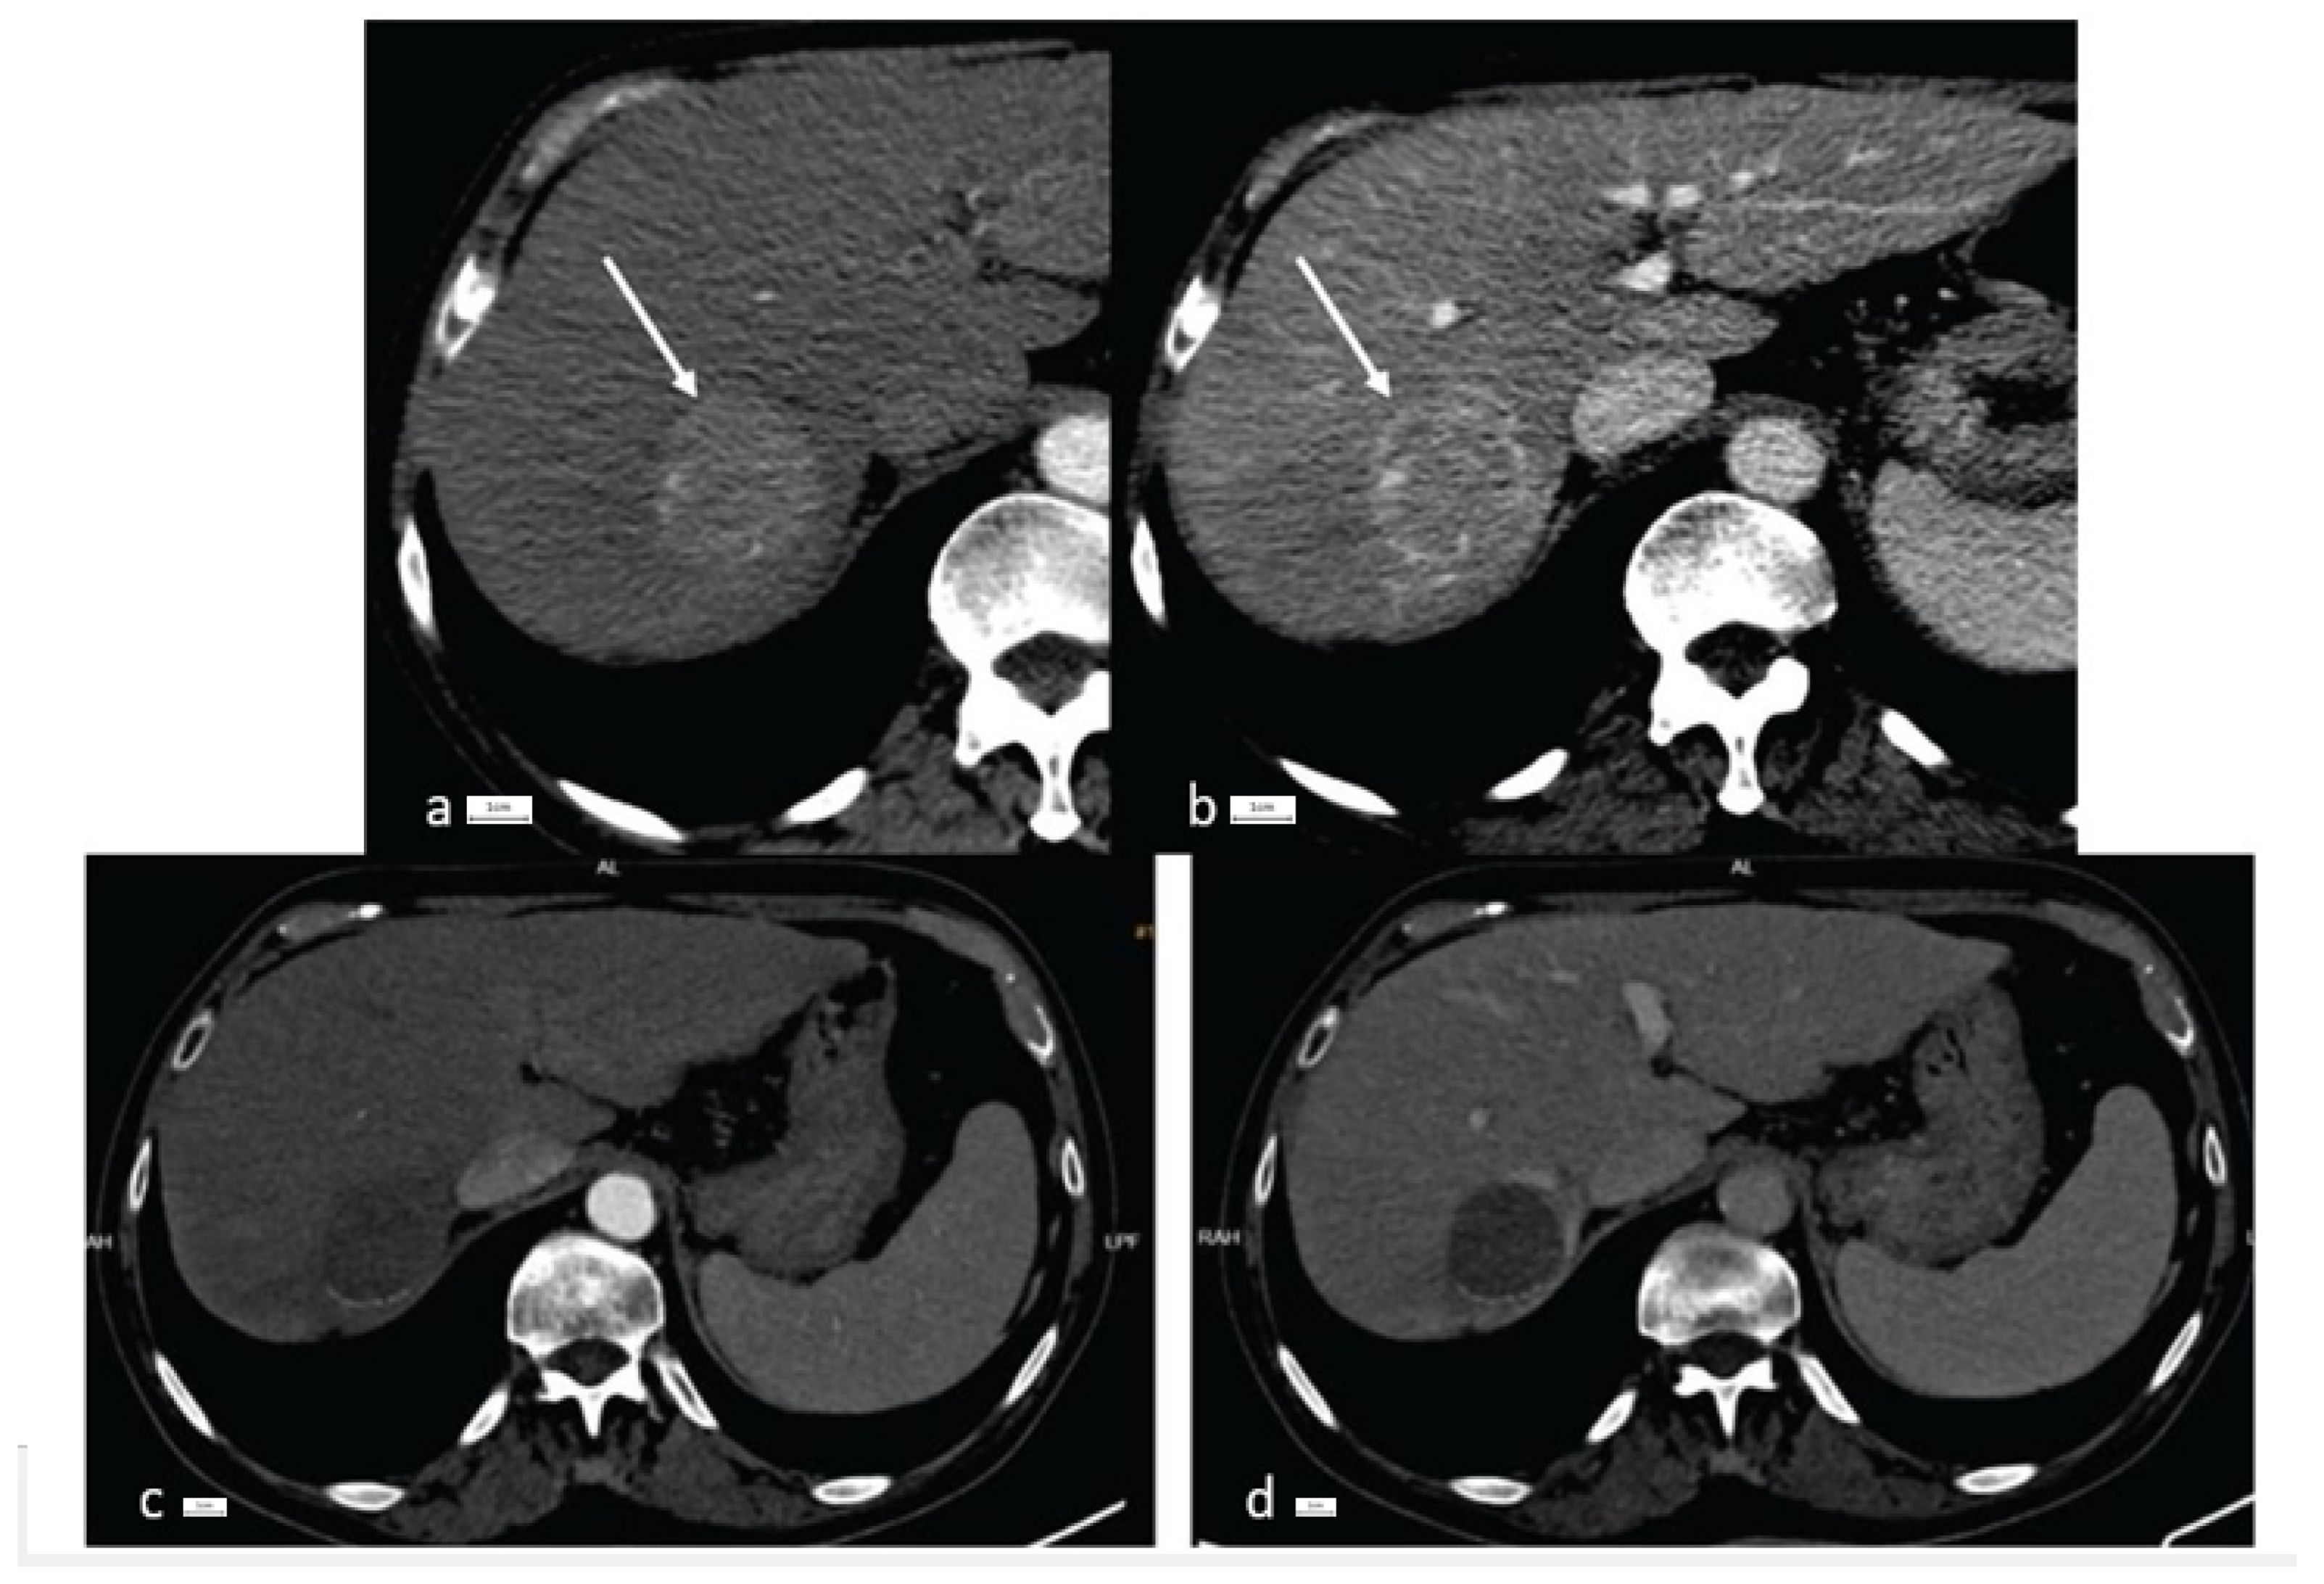

| LI-RADS score | LR-4: 2 patients (20%) LR-5: 8 patients (80%)  | LR-4: 2 patients (22.2%) LR-5: 7 patients (77.7%)  | LR-4: 1 patient (25%) LR-5: 3 patients (75%)  |